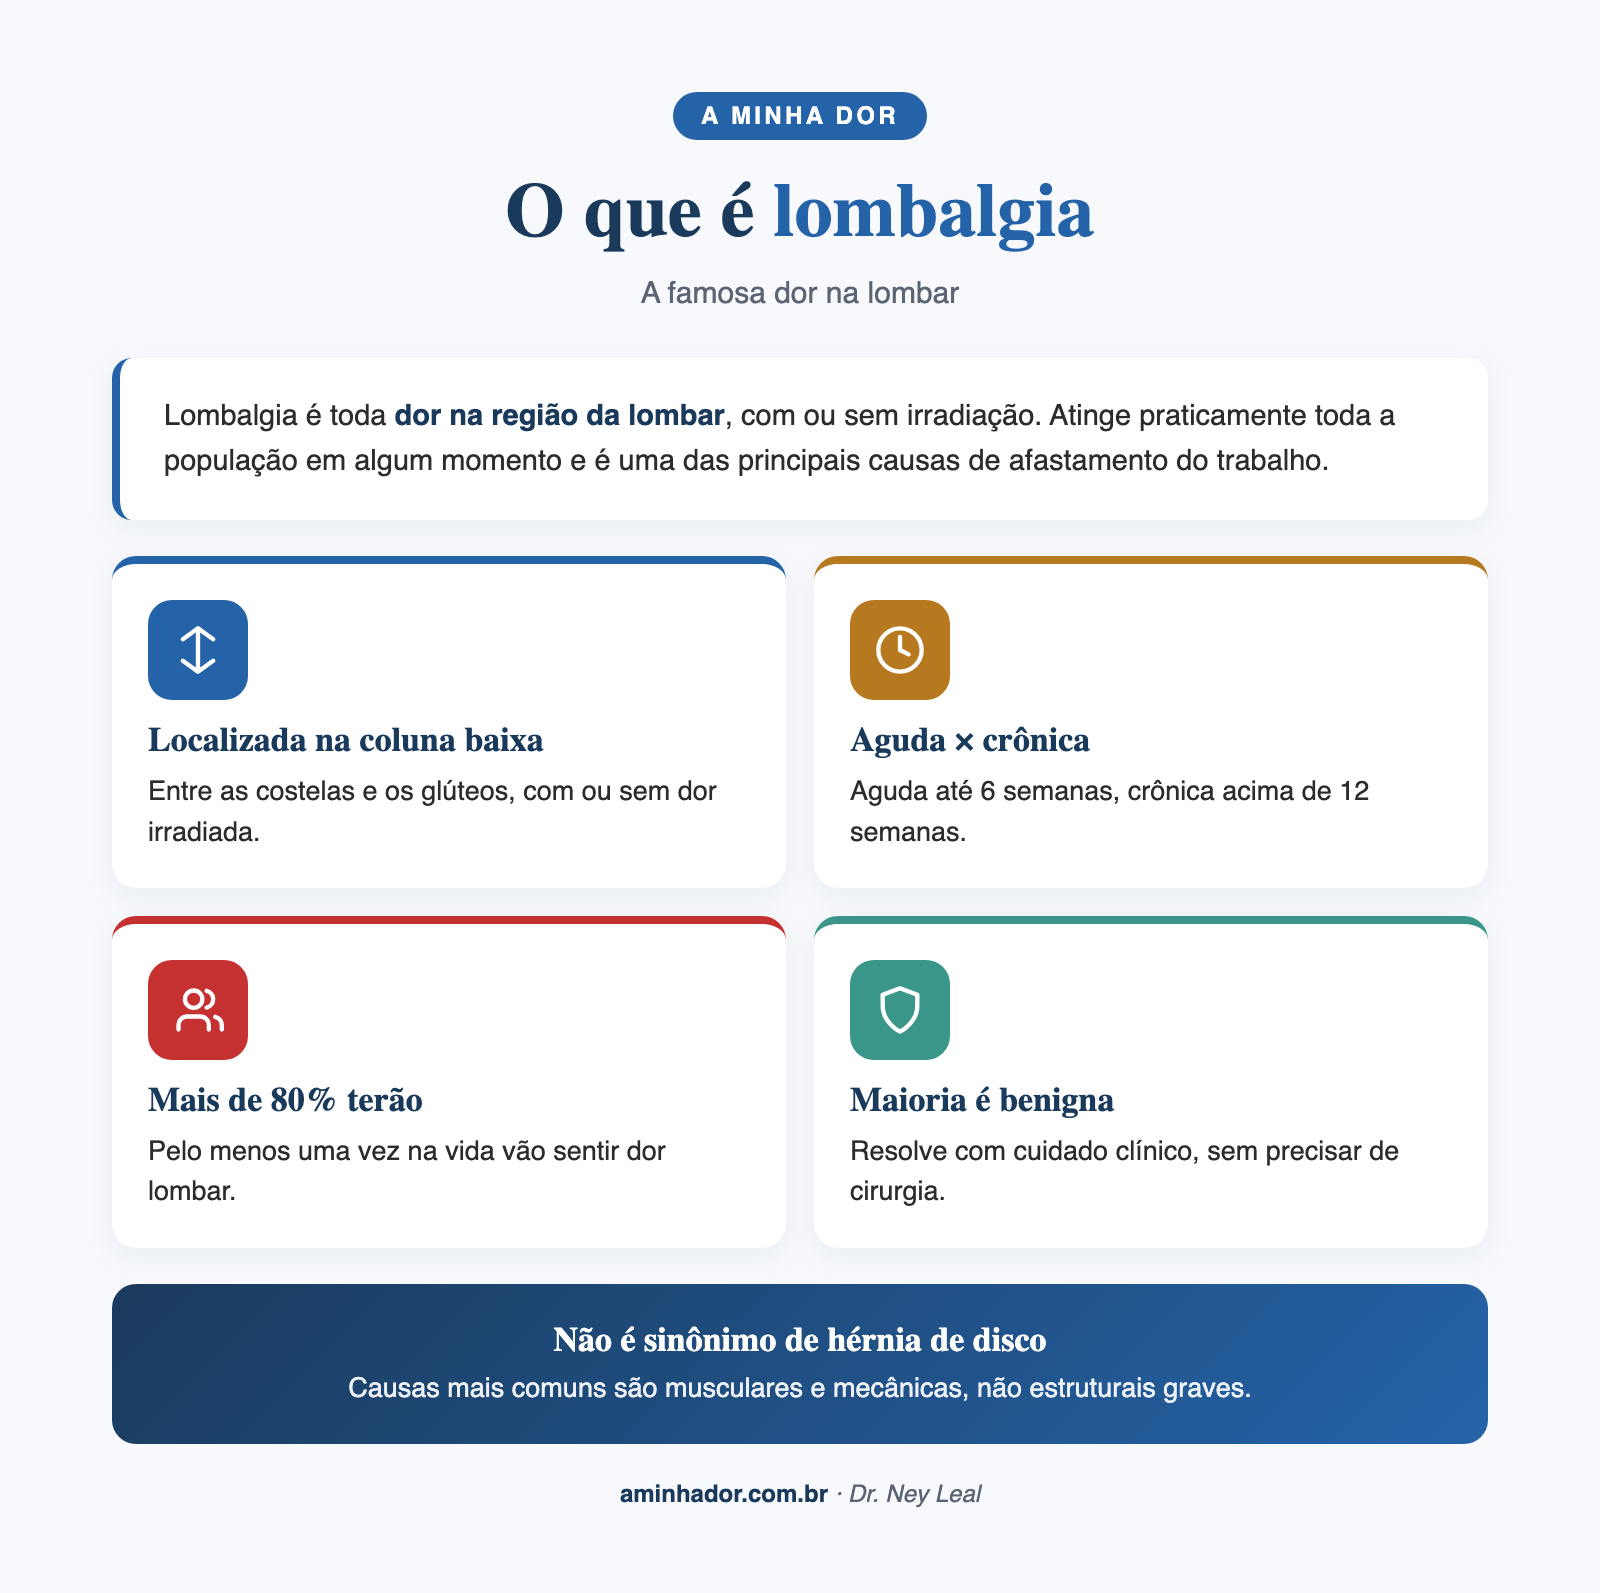

Lombalgia, a famosa dor na parte baixa das costas, é a causa número um de incapacidade no mundo[1]. Estima-se que até 80% das pessoas terão pelo menos um episódio ao longo da vida[2]. Se você está lendo isso com dor nas costas agora, saiba que não está sozinho, e que existem caminhos eficazes pra melhorar.

Lombalgia é o termo médico pra dor na região lombar, a parte inferior das costas, entre as costelas mais baixas e o início das nádegas. Os mais velhos costumam chamar de “dor nas cadeiras”. A dor pode variar de um incômodo leve até uma intensidade que impede qualquer movimento.

Lombalgia aguda

Dura menos de 6 semanas. É a mais comum, geralmente causada por esforço, postura inadequada ou movimento brusco. A maioria melhora espontaneamente em dias ou semanas, com cuidados simples.

Lombalgia subaguda

Dura entre 6 e 12 semanas. Se a dor chegou aqui, precisa de atenção. É o momento de procurar ajuda pra evitar que a dor se torne crônica.

Lombalgia crônica

Persiste por mais de 12 semanas. Nesse ponto, a dor não é mais apenas um sintoma, ela se tornou uma condição em si. O sistema nervoso pode estar sensibilizado, amplificando sinais que antes não eram sentidos como dor. É quando o tratamento multidisciplinar faz mais diferença. Pra entender melhor esse processo, leia nosso guia sobre o que é dor crônica.

Causas mecânicas (mais comuns, cerca de 90% dos casos)[3]: distensão muscular, entorse ligamentar, degeneração dos discos gelatinosos que servem de almofada entre uma vértebra e outra, artrose das articulações, e por aí vai. Essas causas mecânicas não precisam de cirurgia na grande maioria dos casos.